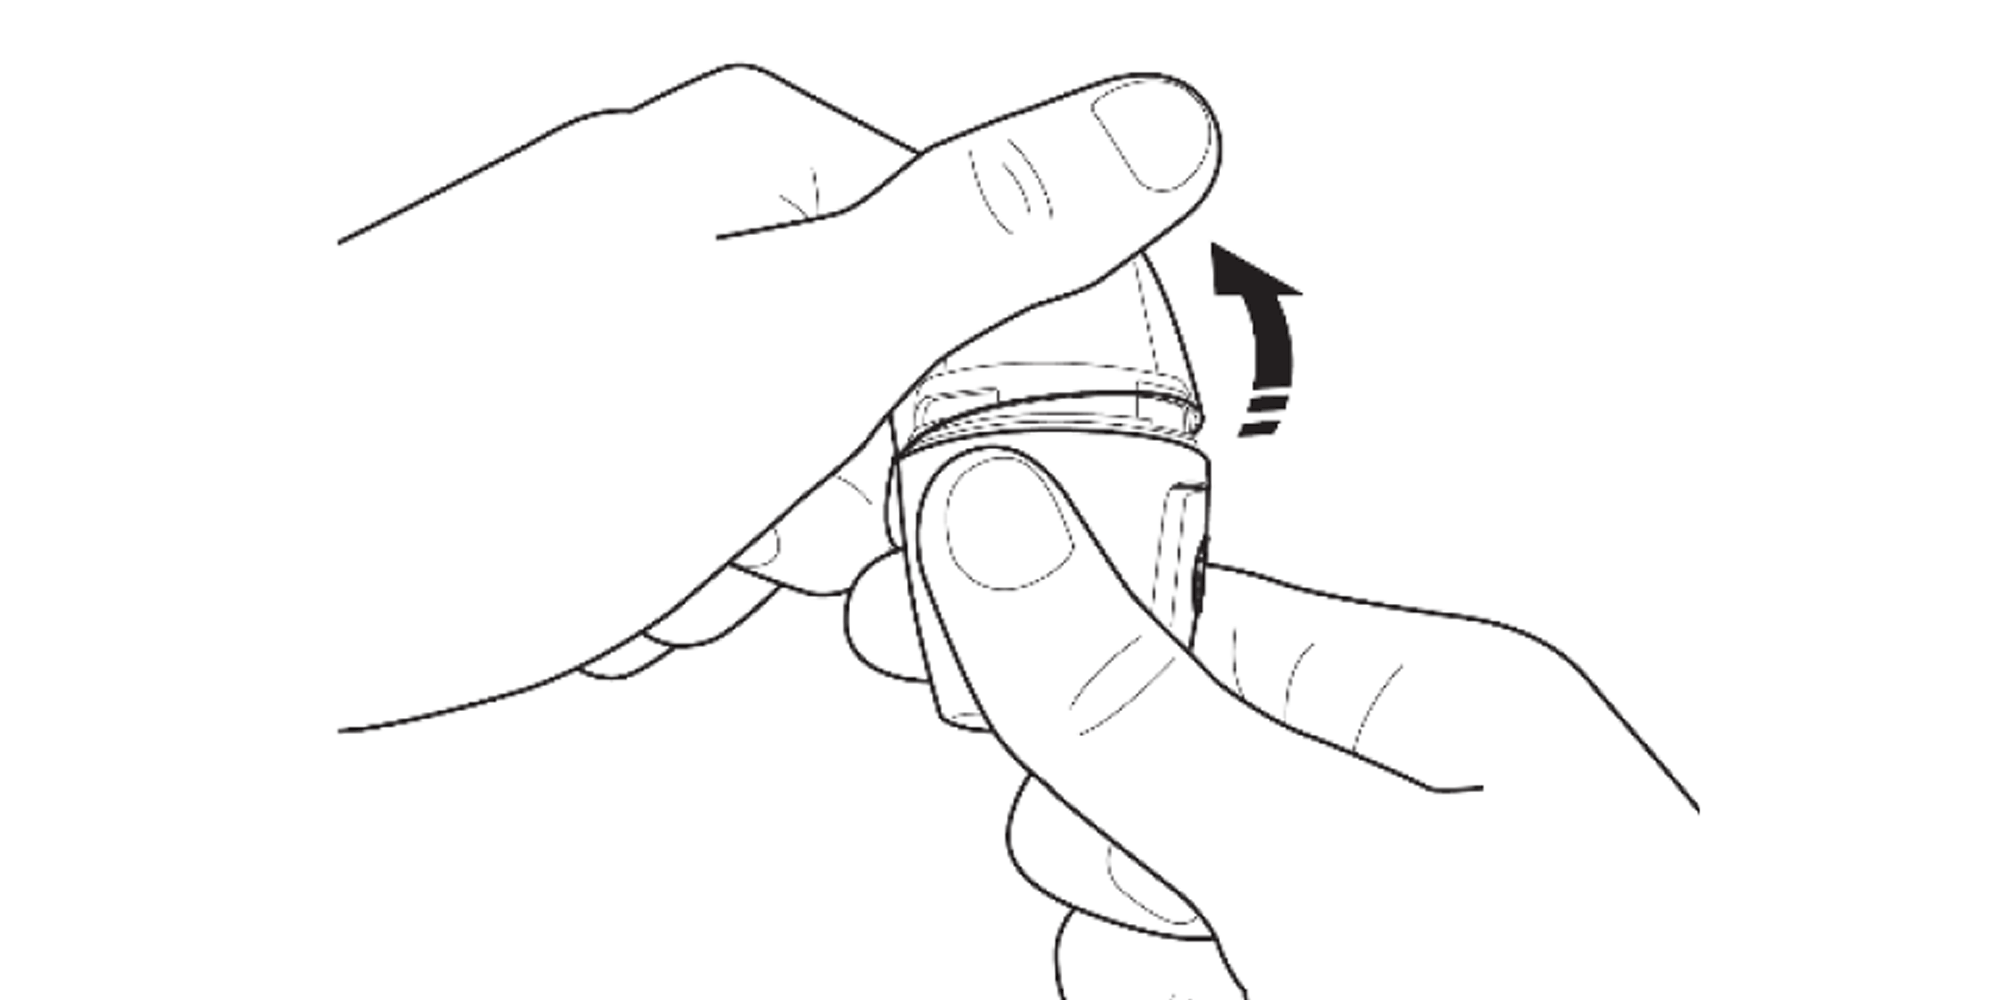

Remove the cap and hold the Vertical-Haler with the mouthpiece upwards.

Press the area marked with a chevron. Pull the mouthpiece up and away from the base.